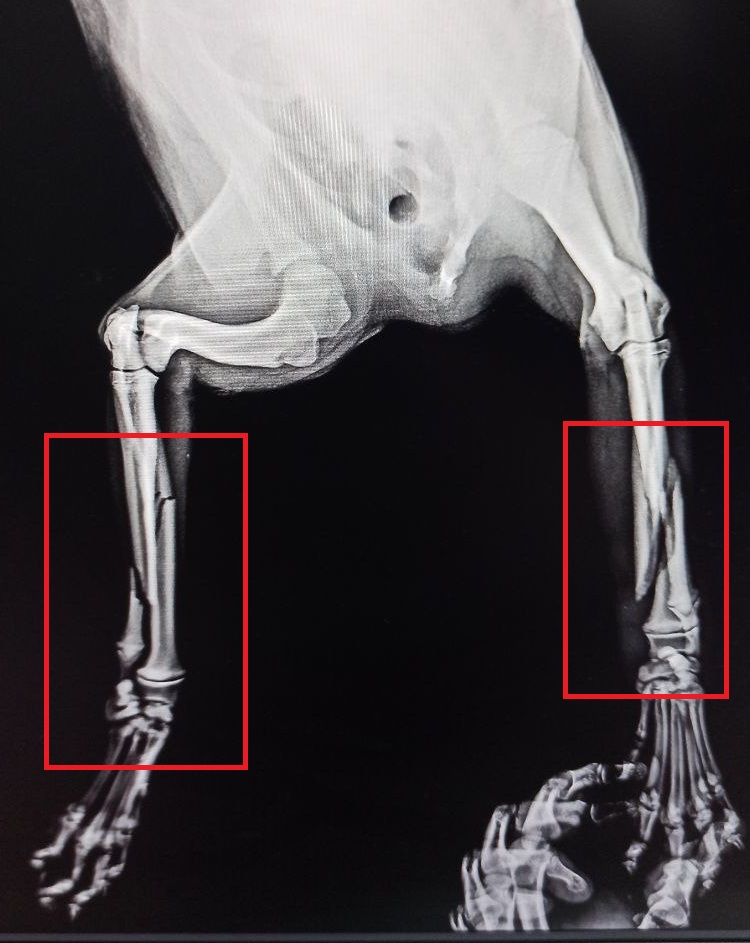

Сегодня утром возле моей работы был обнаружен щенок с перебитыми передними лапами, что именно произошло с ним - неизвестно, но требуется операция.

Сегодня на наркоз и рентген было потрачено 200р, стоимость операции 2300р.

Далее наверняка потребуются ещё медикаменты.

Без операции для собакена к сожалению путь только на усыпление.

Напоминаю историю: во вторник щенка примерно 4–5 месячного скорее всего сбила машина.

Щенок лежал на тротуаре и истекал кровью. У него были переломы обеих передних лапок.

Сегодня ветеринар провел операцию - установили металлические спицы, гипс.

Щенок находится на обезболивающих, антибиотиках, противовоспалительных.